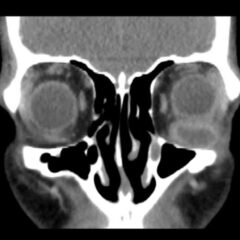

An 18-year-old female presented to the emergency department (ED) with two days of right lower quadrant pain and associated nausea and emesis. After relevant information was gathered and with physical exam findings of a tender right lower quadrant, positive psoas sign, positive Rovsing sign, and pain with right heel tap, the patient was presumed to have appendicitis. However, imaging contradicted the initial leading diagnosis and revealed a markedly distended, hydropic gallbladder with its tip near the umbilicus. Findings of the distended gallbladder with marked wall thickening and pericholecystic fat stranding and edema confirmed acute cholecystitis, and the patient was taken by general surgery for cholecystectomy. Together, this unusual presentation and this unexpected diagnosis shine light upon another facet of the hydropic gallbladder while also serving as a salient reminder to contemplate a broad differential regardless of seemingly classic presentations of illnesses.